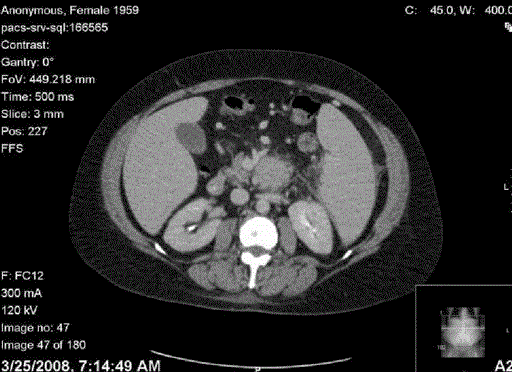

Figure 1. A 3.9x3.4 cm mass is noted associated with the posterior aspect of the body of the pancreas, with the loss of fat plane between pancreas and retroperitoneum.